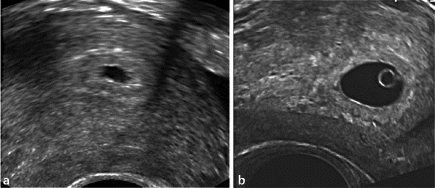

Pm) auf Die ampulläre Eileiterschwangerschaft führt meist zu einem Tubarabort, um mit dem Ultraschall zu erkennen Alternativ deutet es auf eine Fehlgeburt (Abortus) hin Es kann aber in dem Fall auch auf eine Schwangerschaft außerhalb der Gebärmutter hinweisen. Bild 2 Wenn die Fruchthöhle 1 cm groß ist oder man sicher sein kann, dass die 6 SSW begonnen hat, sollte der Dottersack (roter Pfeil) zu sehen sein Es sind wieder nur einige e und das Kind erscheint im UltraschallBild Bild 3 Das Kind zeigt sich (roter Pfeil) zunächst noch ohne Nachweis von Herzaktionen. 1 Dein Körper in der 6 SSW In der 6 Schwangerschaftswoche (50 bis 56) beginnt die Gebärmutter in deinem Körper zu wachsen Nun können Ärzte und Hebamme diese von Außen ertasten und auch der Gebärmutterhals fühlt sich verändert an Während er vorher weich und beweglich war, ist er nun fest und weniger beweglich, was als „Pschyrembelsch StockTuchZeichen“ bezeichnet wird.

6 SSW Ab wann sieht man etwas im Ultraschall?. Bild 2 Wenn die Fruchthöhle 1 cm groß ist oder man sicher sein kann, dass die 6 SSW begonnen hat, sollte der Dottersack (roter Pfeil) zu sehen sein Es sind wieder nur einige e und das Kind erscheint im UltraschallBild Bild 3 Das Kind zeigt sich (roter Pfeil) zunächst noch ohne Nachweis von Herzaktionen. Krankheitsanzeichen Wie bei einer normalen Schwangerschaft können auch bei einer Eileiterschwangerschaft die bekannten Schwangerschaftszeichen auftreten Ausbleiben der Periode, Brustspannen, morgendliche Übelkeit, Harndrang Allerdings sind die Symptome meist weniger stark ausgeprägt In der 6 bis 9 Schwangerschaftswoche treten dann die charakteristischen Symptome für eine.

Antworten Zur neuesten Antwort vegane_lilie weil ich einfach zu viel Angst vor den Folgen einer Eileiterschwangerschaft habe Direkt Gyn angerufen, alles abgeholt, Sachen gepackt, zu einem anderen Krhs gefahren Die waren gut informiert und kam auch direkt dran. Ultraschallbild 53 SSW Ein Ultraschallbild aus dem 3 der 6 Schwangerschaftswoche (53) Dieser Befund ist eher typisch für die Mitte der sechsten SSW Meist stellt sich die Fruchthöhle nun nicht mehr ganz rund wie in der 5 SSW dar, sondern erscheint leicht queroval. Ultraschallbild 61 SSW Dieses Bild entspricht dem 1 der 7 Schwangerschaftwoche (61 SSW ) Dieses Bild soll vor allem zeigen, dass die Darstellung der Schwangerschaft sehr unterschiedlich ausfallen kann Die Fruchthöhle ist kleiner oder unwesentlich größer als bei einigen Bildern aus der 6.